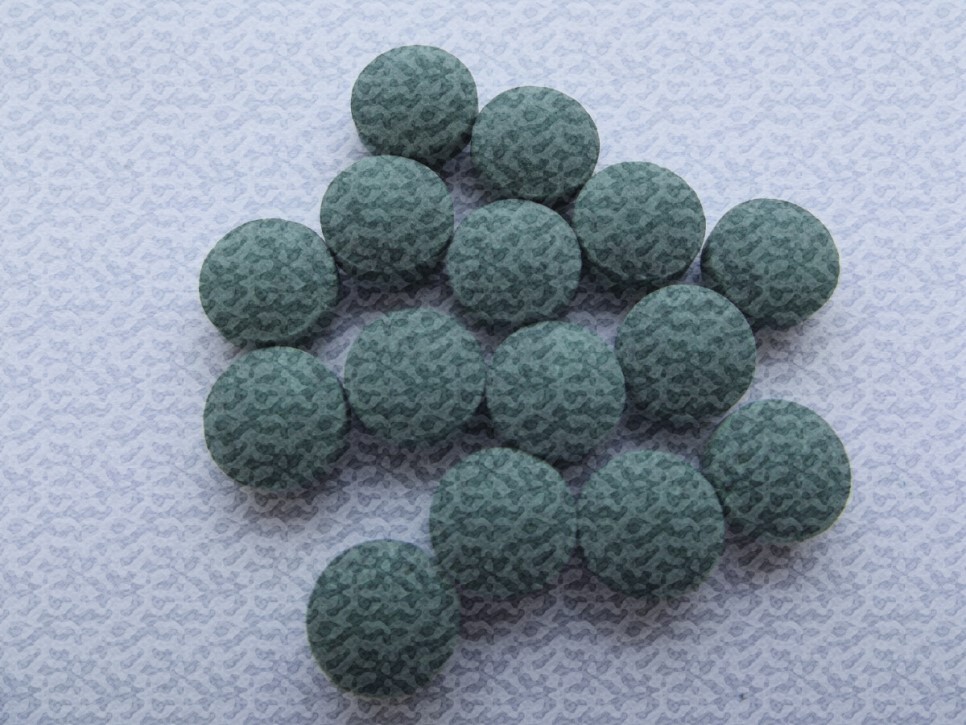

공.진.단. 같은 경우에는 아침에

공복상태에서 복용을 하시는게

가장 효과적이라고 합니다.

일어나자마자 공.진.단. 한알을

약 50회 정도 씹어 드시며

내용물이 모두 가루가

될 정도의 상태에서

물 한모금 정도 해주시면

깔끔히 잘 넘어간다고 합니다.

공진단 먹는법

평소 냉동실에 저장해두었다가

공.진.단.을 복용하기 10분 전

실온에 보관하고 녹은 후에

복용하시는게 좋다고 합니다.

공.진.단. 우황청심원 표면의

금박은 99.9%가 순금입니다.